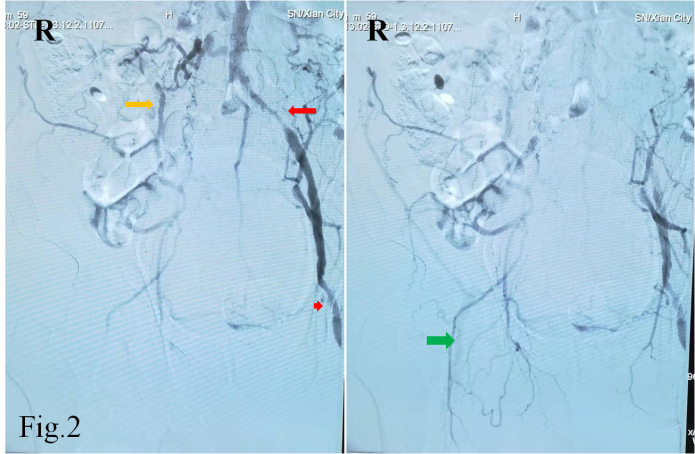

经过导丝引导下,谨慎地将造影导管置于主动脉弓,造影显示Ⅱ型主动脉弓,介入医生顿感压力倍增。常规路径下(股动脉置管),Ⅱ型主动脉弓要比Ⅰ型主动脉弓操作难度复杂的多,颈部血管从主动脉弓发出角度、走形、迂曲度及造影导管在主动脉弓如何塑形、塑形成功率等等都会制约操作时间、顺畅性,稍有不慎可能导致主动脉弓斑块脱落、主动脉动脉夹层等情况发生。增加了在经桡动脉在Ⅱ型主动脉弓上超选造影的难度。经介入医生耐心、细致操作下,反复尝试降主动脉造影导管成型,逐步“逆行”完成全脑血管造影及下肢动脉造影。